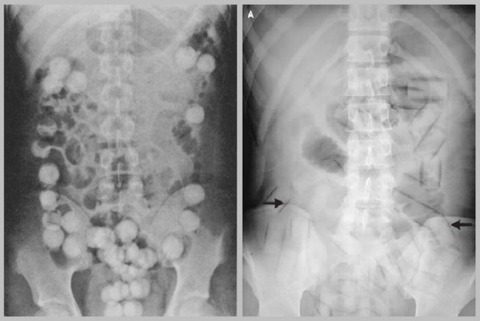

海外からコカインなどの麻薬類を密輸する際、コンドームに詰めて直腸や

膣内に入れて運び込む、運び屋という仕事がありますが数年に一回程度の

割合で飛行機の機内や空港の税関で、体内のコンドームが破れて突然死と

いう例がありますが、あれも吸収の速い直腸や膣内に入れていることから